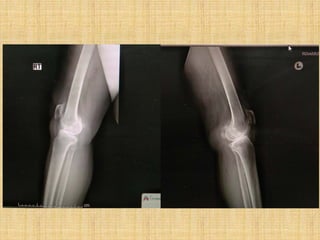

• Imaging

–Weight-bearing view

–Joint space narrowing

–Osteophyte

–Subchondral sclerosis

–Subchondral cyst

• Imaging –Weight-bearing view –Jointspace narrowing –Osteophyte –Subchondral sclerosis –Subchondral cyst